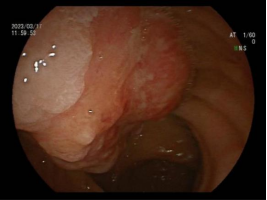

8.内镜下内痔硬化剂及套扎治疗

内镜套扎治疗及硬化治疗 适合I-III期 内痔,包括部分混合痔的微创治疗,疗效显著,与传统外科手术相比,超级微创、费用低、见效快,具有很大优势。

III度内痔 硬化剂及套扎术后